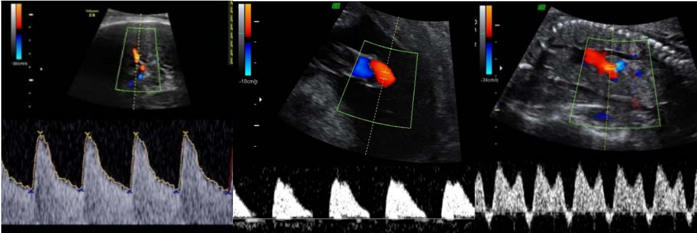

Gestante 28 anos, secundigesta (parto vaginal), na 31ª semana de gravidez. Veio à emergência mostrar resultado de ultrassonografia. No momento, assintomática. Ao exame, estado geral bom, dinâmica uterina ausente, batimentos cardiofetais de 128 bpm e altura de fundo uterino de 21 cm. Pressão arterial de 150 x 100 mmHg. Ultrassonografia com maior bolsão de líquido amniótico de 1,0 cm. Peso fetal estimado de 900g (< 3º percentil). Proteinúria de fita de 2+/4+. Abaixo seguem as imagens da dopplervelocimetria da artéria cerebral média, umbilical e ducto venoso, respectivamente.

Assinale a alternativa CORRETA quanto à conduta, baseada nos critérios diagnósticos da International Society for the Study of Hypertension in Pregnancy.